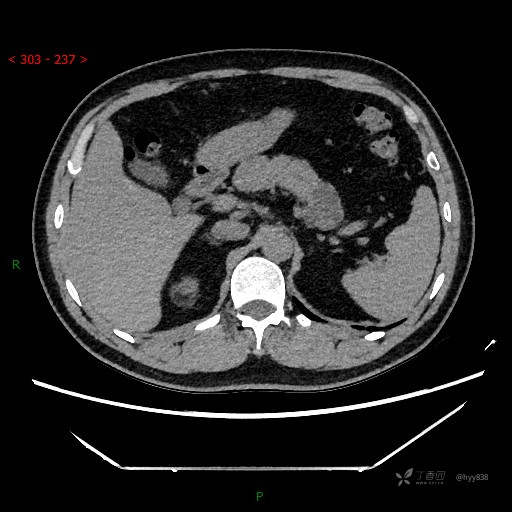

腹部CT平扫